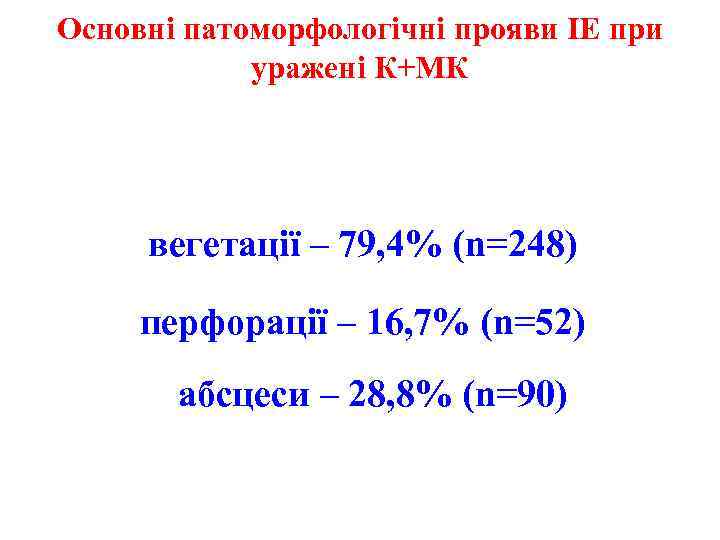

Основні патоморфологічні прояви ІЕ при уражені К+МК вегетації – 79, 4% (n=248) перфорації – 16, 7% (n=52) абсцеси – 28, 8% (n=90)